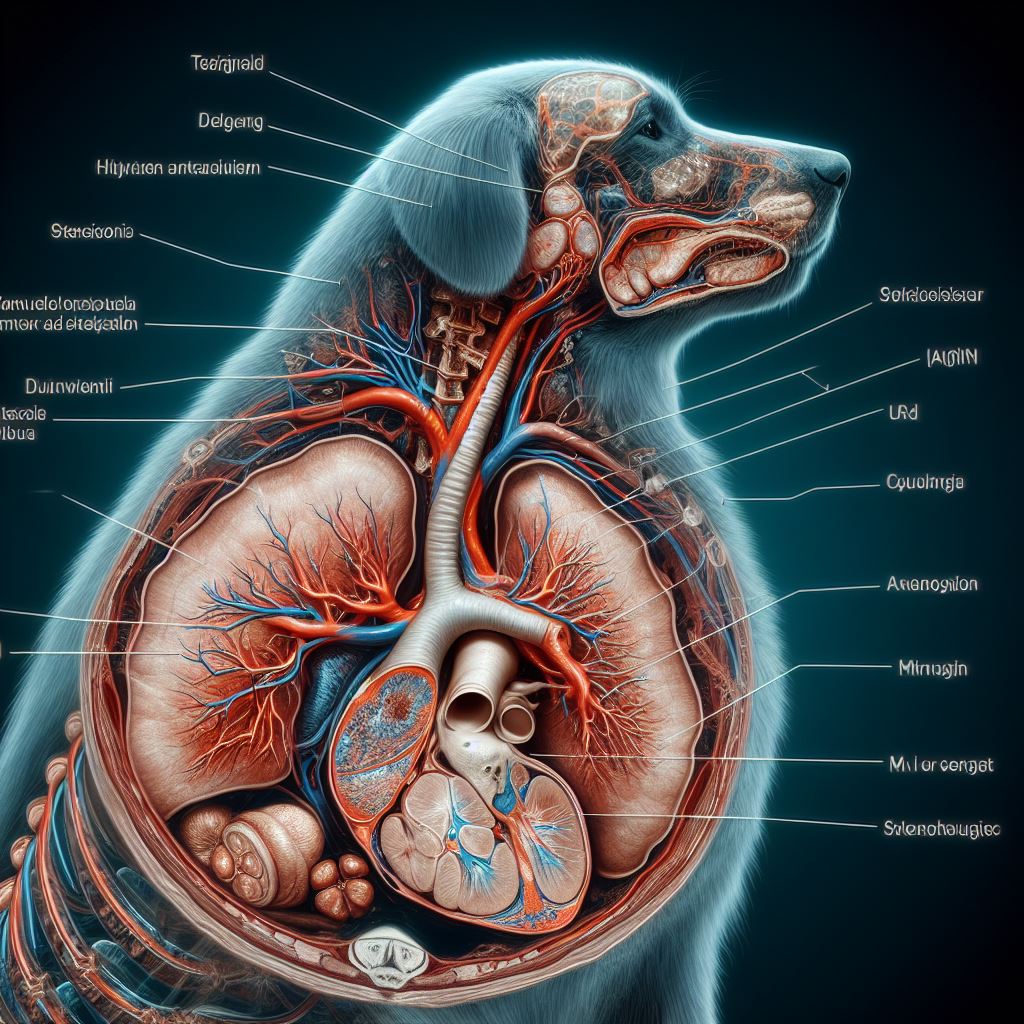

강아지 기관지 협착증 원인과 증상, 치료 방법 알아보기 사진